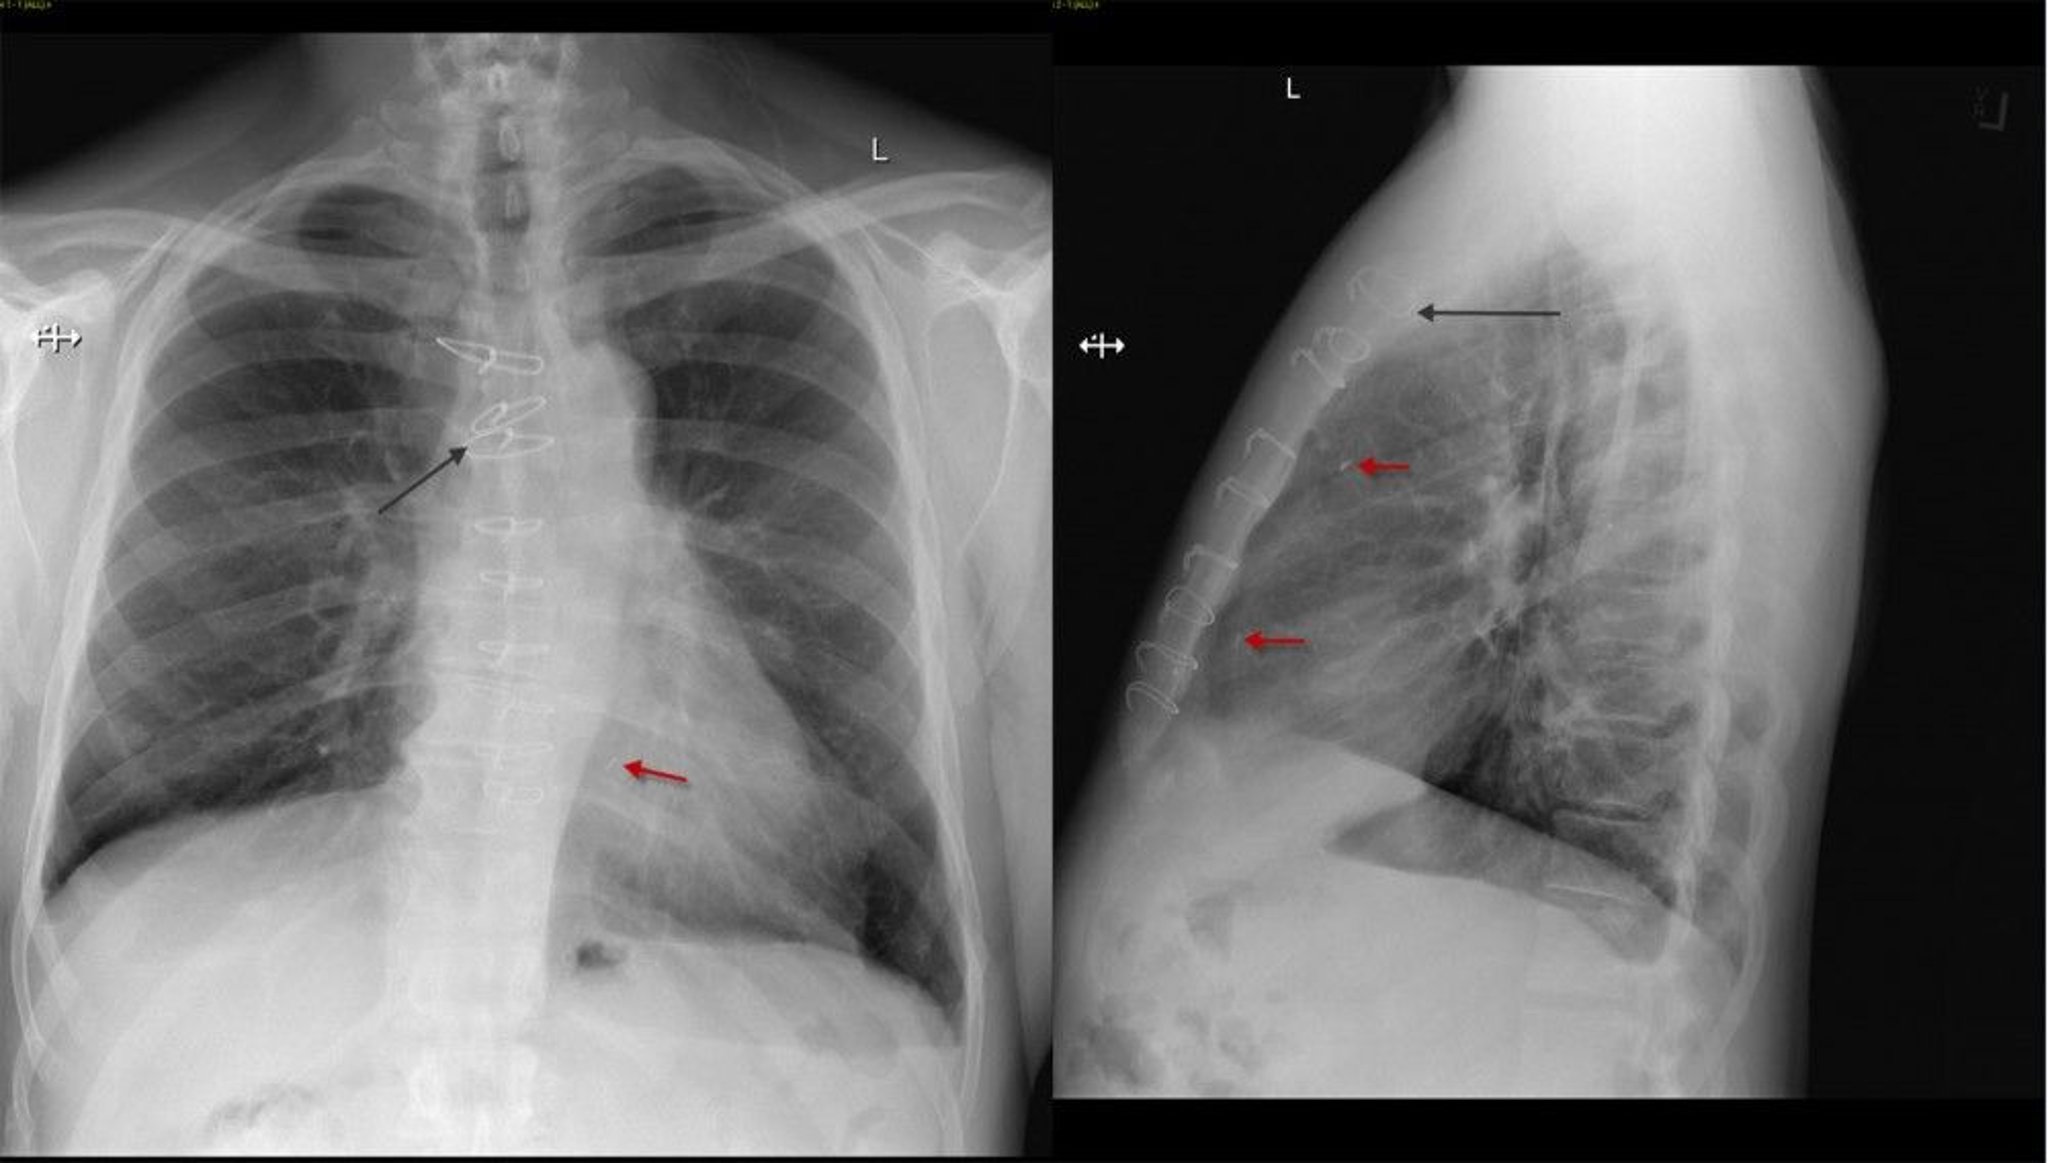

Röntgenthorax eines Patienten nach koronarer Bypass-Operation

Frontale und laterale Thoraxröntgenaufnahme eines Patienten nach koronarer Bypass-Operation mit Sternumnähten (schwarzer Pfeil) und chirurgischen Clips (roter Pfeil).